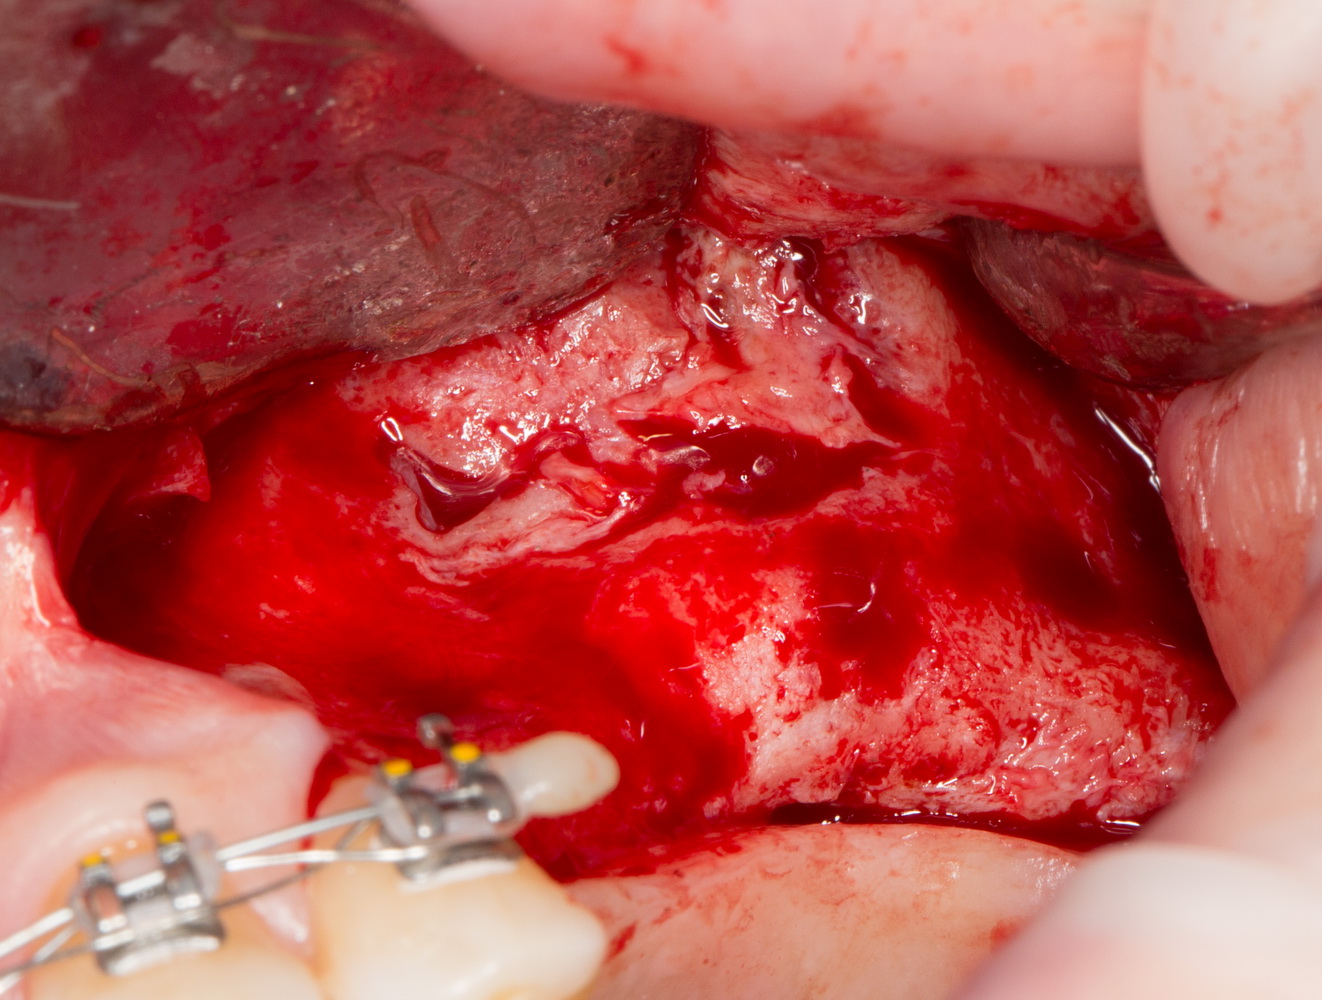

Сначала убираем все грануляции и измененные ткани. На перфорации слизистой не обращаем внимания — с ними разберемся позже:

7  8

Как видите, после удаления «всего лишнего» получился значительный дефект? Большинство хирургов на этом этапе действительно приунывают и сворачивают операцию, мотивируя это тем, «что в данных условиях невозможно что-то восстановить».